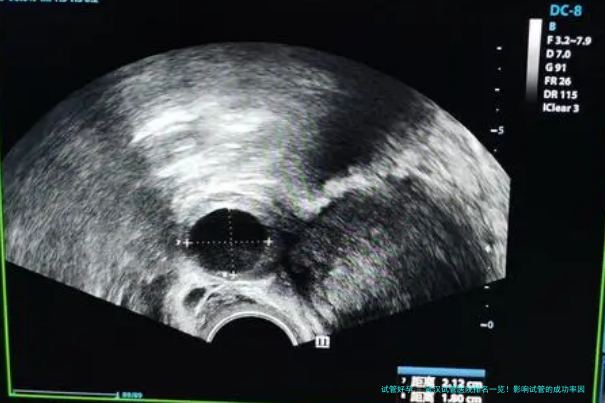

武汉试管医院排名一览!影响试管的成功率要素有哪些?根据国家卫生和计划生育委员会的最新消息,此刻武汉有三十二家生殖机构可以开展人类辅助生育技术,其中武汉有十家生殖机构可以发展试管受精。关于不行产生有效卵子的性来说,试管婴儿是一种希望。

2影响试管成功率的因素